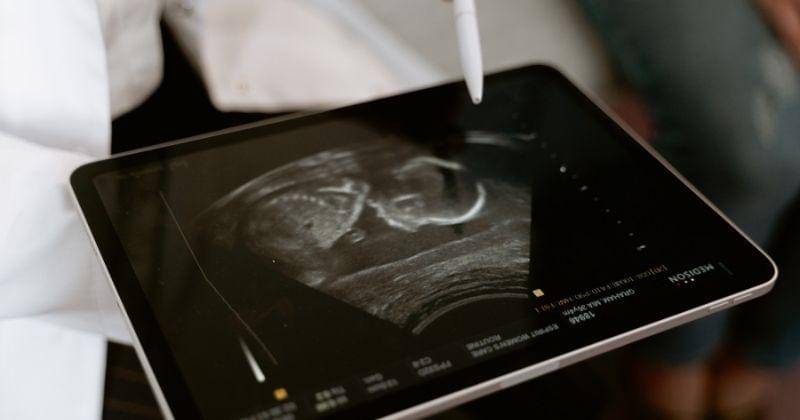

2. Berdasarkan hasil USG

Salah satu alasan kenapa ibu hamil sebaiknya rutin memeriksakan diri adalah untuk melihat apakah ada kemungkinan bayi mengalami cacat lahir. Hal paling awal yang bisa Mama lakukan adalah mengamatinya lewat USG. Dengan demikian, Mama bahkan bisa mengetahui risiko ini sejak trimester pertama.

Pengamatan lewat USG pada trimester awal memang tidak selalu memberikan hasil yang akurat. Namun dokter akan melihat posisi, ukuran, bentuk, dan penampakan lain untuk mengetahui kondisi bayi. Jika memang ada potensi kecacatan, maka sejumlah tes akan dilakukan.

Seiring dengan bertambahnya usia kehamilan, maka pengamatan akan lebih mudah dilakukan. Maka akan dapat mengetahui apakah janin memiliki anggota badan lengkap dan memiliki fisik normal. Selain itu, dokter juga akan mengamati apakah organ-organ calon bayi berfungsi dengan normal.